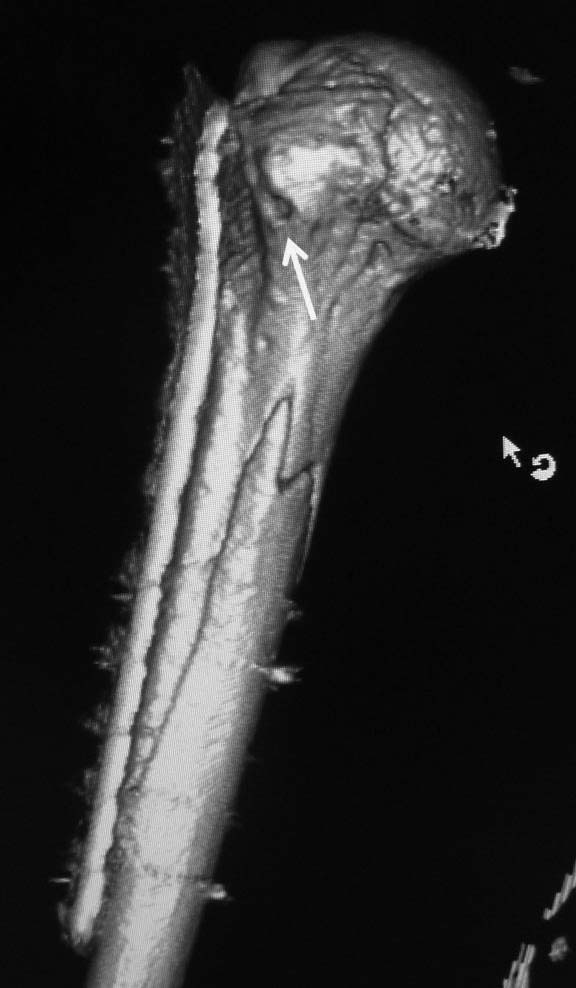

Позвольте поделиться очередной такой находкой. С подобным сочетанием раньше встречаться не доводилось. Пациент 44 лет. На рентгенограммах простой перелом диафиза плечевой кости. Выявленный на КТ вдавленный перелом головки по рентгенограммам нельзя было заподозрить даже ретроспективно, после выполнения КТ.

Наряду с остеосинтезом диафиза выполнена репозиция вдавленного перелома головки через отверстие в малом бугорке (обозначено стрелкой). Сформировавшаяся после репозиции полость заполнена аутостружкой с крыла подвздошной кости.